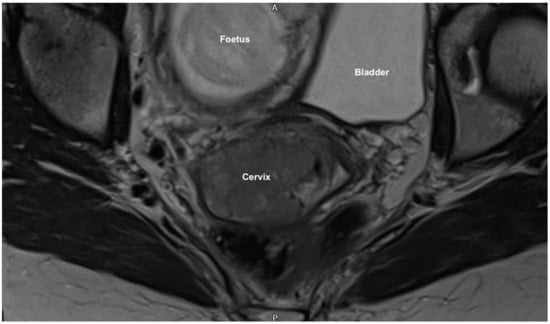

2.2. Clinical Findings

2.3. Diagnostic Assessment